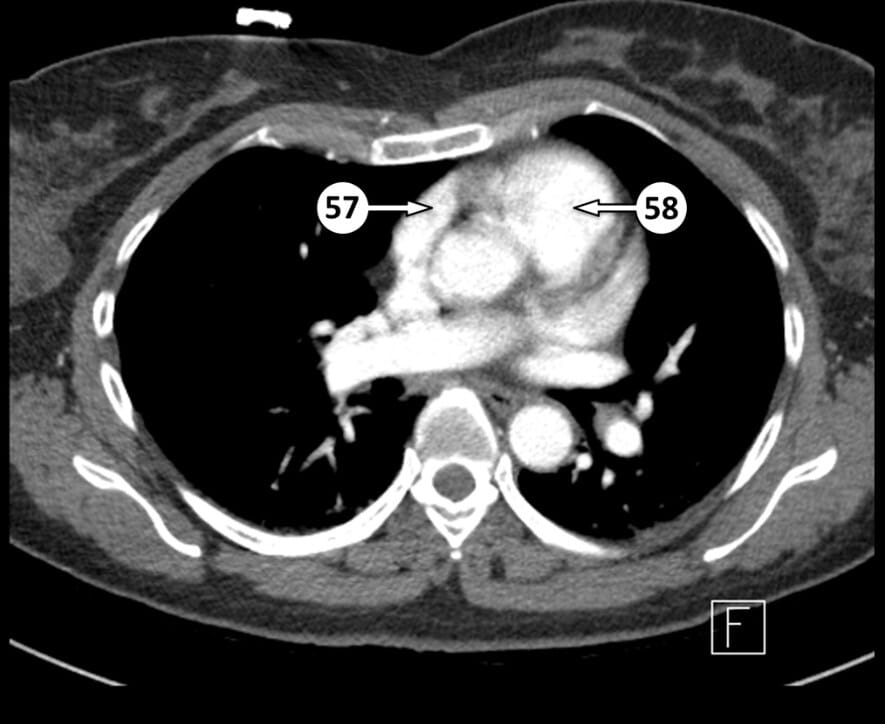

57. right atrial appendage

58. pulmonary valve (approximate location)